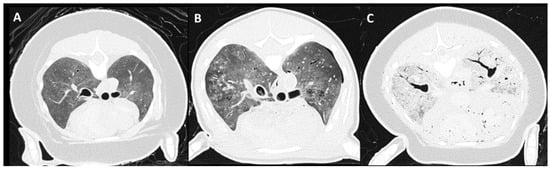

3.4. Pulmonary Parenchymal Attenuation Changes